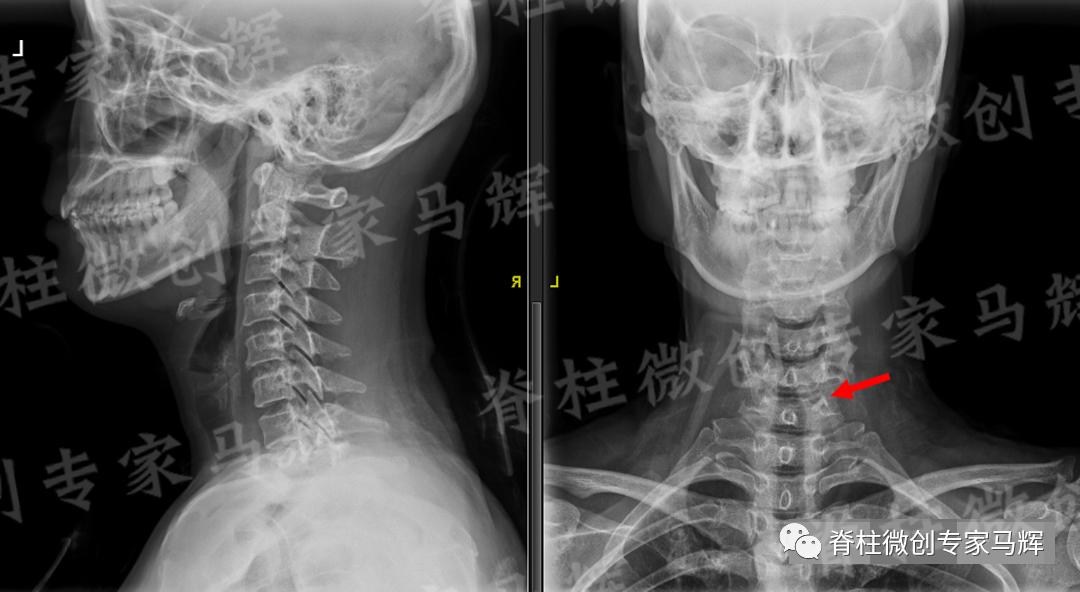

经过充分准备,一周后马主任带领手术团队为患者做了颈椎后路经皮内镜下颈椎间盘髓核摘除术。手术过程十分顺利,仅用时45分钟,且手术切口很小,约8毫米。

术后疼痛完全缓解,第一天便下床活动,第二天就办理出院了。

(术后)